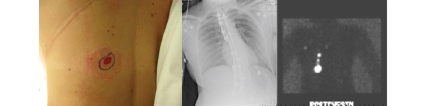

10.4.2 Aberrant or Interval Drainage Patterns

Fig. 10.3).